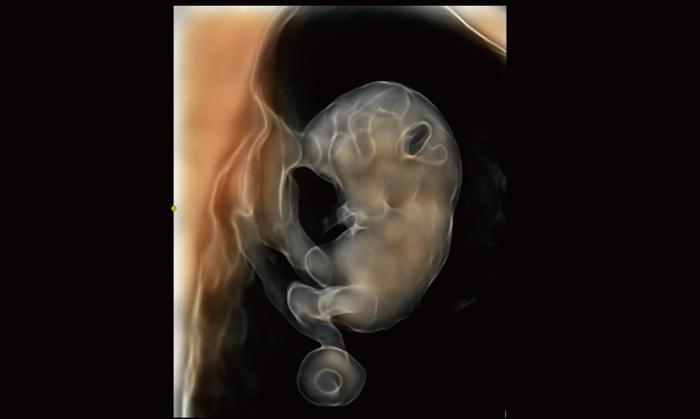

Care este diferenta dintre ecografia 2D, 3D si 4D?

Foto 1/7